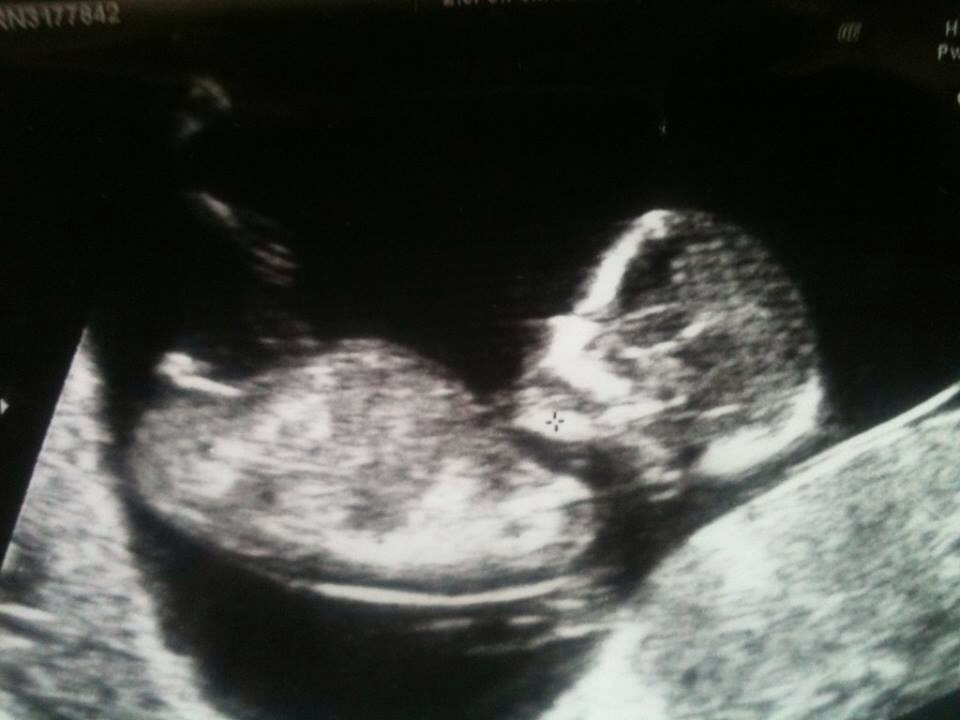

For a friend u have permission to ask gender Attachment 15303

GIRL!!!!

Boy

It looks slightly angled with that bulb on the end- that is not a fork to me so that is why I said boy. Just a guess!

I would guess boy

I'm guess girl.

This is a hard one, I am leaning towards a boy